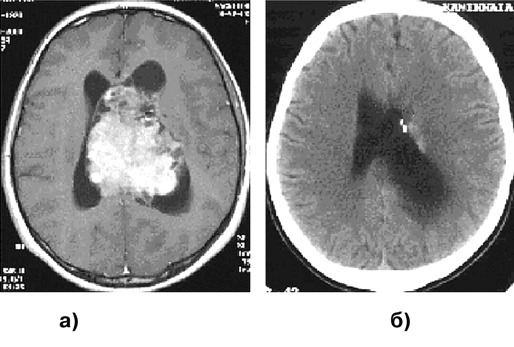

На КТ плотность опухоли весьма гетерогенна (рис. 4а). Центральная зона низкой плотности представляет некроз, выявляемый в 95% случаев. Границы опухоли нечеткие. Петрификаты встречаются редко. Часто определяются кровоизлияния различной давности. Опухоль обычно окружена зоной перифокального отека, распространяющегося в белом веществе больших полушарий. ГБ обычно активно накапливают контраст. Усиление после введения контрастного вещества выражено часто неоднородно, контрастирование имеет характерный вид кольца с неоднородным внутренним контуром. В ряде случаев ГБ отсутствует узловой компонент, и опухоль растет инфильтративно, широко поражая полушарие. Рентгенологически признаки повреждения ГЭБ (накопление контраста) при этом нередко отсутствуют, и контрастное усиление мало изменяет характеристику сигнала от опухоли.

МР-проявления ГБ в целом отражают патоморфологические изменения, демонстрируя значительную гетерогенность опухоли. На Т1-взвешенных томограммах выявляется плохо отграниченное объемное образование со смешанным (изогипоинтенсивным) сигналом, центральным некрозом, которому соответствует сниженный по отношению к опухолевой массе сигнал (рис. 3в, 4в). На Т2-взвешенных изображениях выявляются участки гипо-, изо-, гиперинтенсивного сигнала от стромы ГБ, зоны некроза, кист и кровоизлияний. Выраженный “масс-эффект” и распространенный отек белого вещества часто сопровождают и небольшие по размерам опухоли (рис. 4б). Границы опухоли сливаются с перифокальным отеком.

Рисунок 4. Глиобластома правой височно-теменной области, распространяющаяся на подкорковые узлы:

а — КТ с контрастным усилением; б — МРТ, Т2-взвешенные изображения; в — МРТ, Т1-взвешенные изображения, с контрастным усилением; г — каротидная АГ

Как и при АА, опухолевые клетки ГБ могут быть обнаружены за пределами зоны усиления сигнала и перифокального отека, выявляемых при МРТ. ГБ широко и быстро распространяются по трактам белого вещества. Типично также распространение на противоположное полушарие через мозолистое тело, переднюю и заднюю комиссуры, реже вдоль внутренней и наружной капсул (рис. 5а, б, г). При полушарных ГБ иногда определяется распространение опухоли в ножки мозга и в заднюю черепную ямку.

Так как ГБ часто бывают сильно васкуляризованы (рис. 4г), то на МР-томограммах, особенно Т2-взвешенных, могут выявляться сосуды опухоли (рис. 4б). В 5% наблюдений встречаются множественные ГБ (рис. 5в), для дифференциального диагноза с метастазами необходима стереотаксическая биопсия.

Рисунок 5. Примеры роста и распространения глиобластомы (МРТ, Т1-взвешенные изображения с контрастным усилением, аксиальная проекция):

а — "передняя бабочка" — глиобластома медиальных отделов обеих лобных долей, больше слева и колена мозолистого тела; б — "задняя бабочка" — глиобластома медиальных отделов теменно-затылочных с обеих сторон, больше справа и валика мозолистого тела; в — первично-множественный рост глиобластомы; г — перивентрикулярное распространение глиобластомы, больше вокруг передних рогов обох боковых желудочков